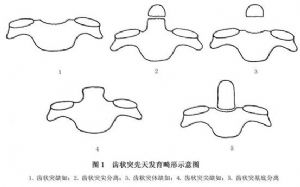

亦非少见,尤其是儿童,主因咽后部慢性炎症造成局部肌肉、韧带及关节囊的水肿、松弛及局部骨质脱钙而引起横韧带的松动、撕脱,并逐渐引起寰椎向前脱位。因其发生过程缓慢,神经症状一般较轻;但如附加外伤因素,则易招致意外。此外侵及颈段的类风湿性关节炎患者,亦有20%左右病例可能出现此种后果。因齿状突畸形亦易引起寰枢脱位,常见的畸形见(图1)。在同样外伤情况下,其更易引起脱位。